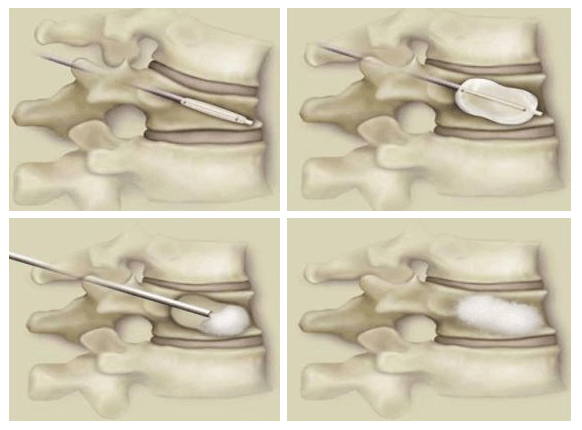

dz¼± ôÃß ¼ºÇü¼ú

°æÇÇÀû ôÃßü ¼ºÇü¼ú°ú ºñ½ÁÇϳª 3ÁÖ°£ÀÇ Àû±ØÀû º¸Á¸Àû Ä¡·á¿¡µµ Áõ»óÀÇ È£ÀüÀÌ ¾øÀ» °æ¿ì ÂîºÎ·¯Áø °ñÀý ºÎÀ§¿¡ ³¡¿¡ dz¼±ÀÌ ´Þ¸° ±ä Ư¼ö ±â±¸¸¦ »ðÀÔÇÏ¿© dz¼±À» ºÎÇ®·Á ³ôÀ̸¦ º¹¿øÇÑ ÈÄ¿¡ '°ñ½Ã¸àÆ®'¸¦ ÁÖÀÔÇÏ´Â ½Ã¼ú·Î ÀåÁ¡Àº ³ôÀ̸¦ ¾à°£ ȸº¹½Ãų ¼ö ÀÖ°í Á» ´õ µÈ »óÅÂÀÇ ½Ã¸àÆ®¸¦ ÁÖÀÔÇÒ ¼ö ÀÖ¾î ½Ã¸àÆ® À¯ÃâÀÇ À§Ç輺À» ÃÖ¼ÒÈÇÒ ¼ö ÀÖ½À´Ï´Ù.